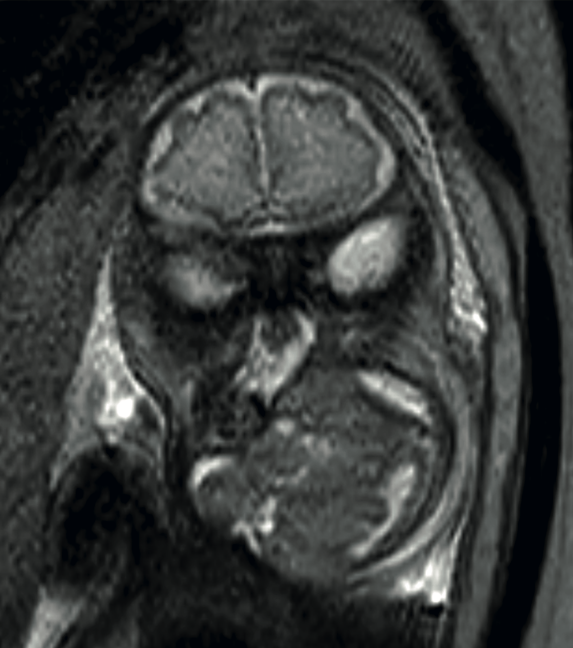

Caso 1

Paciente de 26 años, con diagnóstico de tumoración cervical en el feto a las 29 semanas, con polihidramnios, ultrasonido y resonancia magnética con reporte de tumoración en la región cervical anterior y derecha (8.1 x 7.3 cm), redondeada, con bordes debidamente limitados, contenido heterogéneo y con algunas regiones hiperecogénicas: sólido y quístico, con septos, sin vascularidad interna. El recién nacido se obtuvo, por cesárea, a las 38 semanas, con peso de 3590 g, Apgar 8-9, llanto sostenido, con apnea a los 10 minutos que obligó a la intubación. En el ultrasonido se advirtió una tumoración quística. A las 48 horas se insertó un catéter para drenaje y aplicación de doxiciclina en tres ocasiones. En virtud del tamaño del tumor y afectación de la ventilación se procedió a la traqueostomía y resección del tumor a los 25 días de vida. Se dio de alta del hospital con la traqueostomía. Figura 1

<strong>Figura 1</strong>

Figura 1. Resonancia a las 32 semanas, secuencia T2, feto con hiperextensión del cuello, secundaria a lesión quística, con escaso componente sólido en el hemicuello derecho.